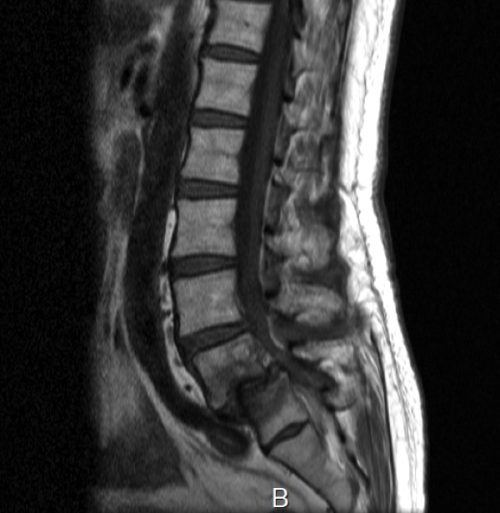

整形外科でレントゲンやMRI検査を受けた結果、腰椎に大きなズレがある「腰椎すべり症」と診断されました。